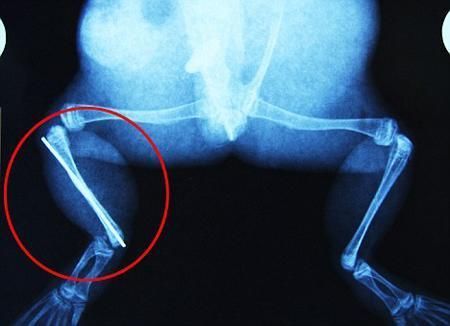

布魯萊的主人,居住在南非約翰內(nèi)斯堡附近的62歲的安妮·米恩斯說(shuō):“我對(duì)這只青蛙如此關(guān)心,人們一定認(rèn)為我瘋了,但是我無(wú)法眼睜睜看著它那么痛苦。青蛙因其靈活的腿腳而著稱,一想到布魯萊的腿里要留下一個(gè)薄金屬片,我就感到心痛。然而我知道,如果不進(jìn)行手術(shù),布魯萊以后就沒(méi)辦法動(dòng)彈了。因此我匆匆趕到獸醫(yī)那里,央求他給這只可憐的青蛙動(dòng)手術(shù)。這位獸醫(yī)整天救助小貓小狗,他很難理解為什么我這么擔(dān)心一只青蛙,但是最終他還是答應(yīng)了給布魯萊做手術(shù)。手術(shù)后是幾個(gè)小時(shí)的焦急等待,我們希望它能快快蘇醒過(guò)來(lái)。不過(guò)現(xiàn)在它的傷口已經(jīng)愈合,又能在花園里跳來(lái)跳去了。X光照射顯示,它會(huì)恢復(fù)的跟以前一樣!

野生生物專家安妮經(jīng)常為學(xué)校寫(xiě)教材,她認(rèn)為這是人類第一次通過(guò)手術(shù)給一只青蛙接斷腿。在手術(shù)開(kāi)始階段,獸醫(yī)把少量給狗用的麻醉藥注入到這只青蛙體內(nèi),讓它失去知覺(jué)。然后他在布魯萊的斷腿上切開(kāi)一個(gè)小口,把一根小鋼針植入腿里。最后獸醫(yī)給它縫了9針,把切口縫合在一起。僅僅幾周后,布魯萊就能在安妮家附近活動(dòng)了。這只青蛙大約已有25歲,主要以嚙齒動(dòng)物、蛇和其他青蛙為食。布魯萊所屬的牛蛙種群正在不斷減小,目前只能在非洲南部的濕地里才能看到這種青蛙。